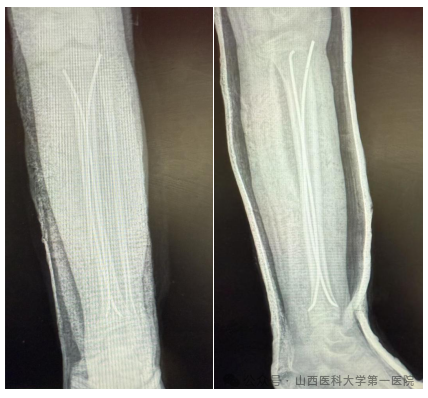

手术切口取双侧胫骨近端骨骺下方1cm长度仅约1cm的纵行切口,预先体外将弹性髓内钉预弯,预计弧顶位于骨折断端,C臂透视下行骨折断端手法复位,复位满意后从两侧切口依次插入2枚弹性髓内钉,使各自弧顶在骨折断端处呈“)(”,给予骨折断端足够支撑,避免骨折断端移位。手术过程顺利,术后复查拍片可见骨折复位满意。